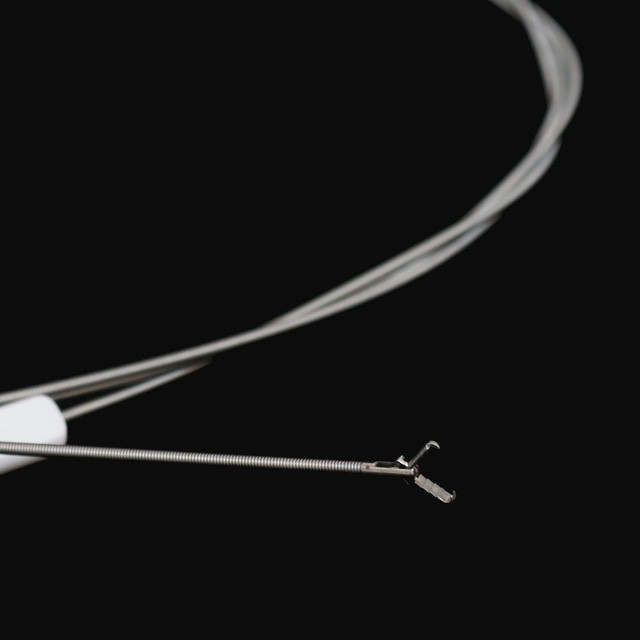

പ്രോംഗ് തരം

FG -28 U-B3 |

3- പ്രോംഗ് തരം |

FG -28 U-B4 |

4- പ്രോംഗ് തരം |

FG -28 U-B5 |

5- പ്രോംഗ് തരം |